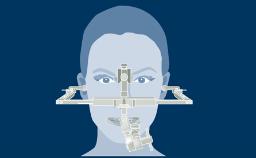

Structured Assessment and Treatment Planning

It also involves the consumer, whose needs must be understood. The consumer or patient must also understand the costs and benefits that are associated with each treatment alternative.

This module will provide information to use when discussing the most appropriate therapeutic approach with individual patients.